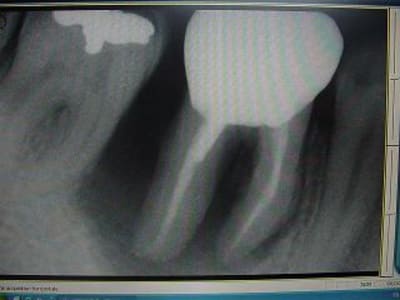

voici un cas paro qui me pose problème: Homme 39 ans, non fumeur, exellente santé ( spotif +++). PAJ dans un mauvais contexte occlusal ( bout à bout et contact essentiellement en posterieur. Je suis un peu paumé sur ce coup là! surtout sur le devenir des molaires. Des pistes avant d'en parler à nice? merci

ci joint des retro de mars 2001 et aout 2003 de 46 qui montre l'evolution du cas..